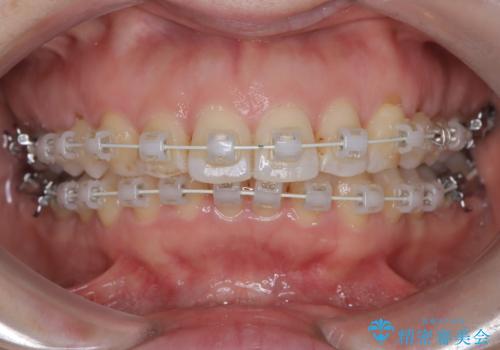

審美装置を用いたワイヤー矯正|非抜歯で歯の凸凹を改善

- 患者様は**歯の凸凹(叢生)**を気にされて来院されました。診査の結果、歯列のスペースが不足しているものの、抜歯をせずに改善できる状態でした。そこで、目立ちにくい審美装置(白いブラケットとホワイトワイヤー)を使用したワイヤー矯正を提案しました。歯列のアーチを広げながら、適宜IPR(歯の幅をわずかに調整する処置)を行い、非抜歯で自然な歯並びへと導く計画を立てました。

治療では、白いブラケットとホワイトワイヤーを使用し、矯正装置が目立ちにくいよう配慮しました。歯列を拡大しながら適切に歯を移動させ、IPRを併用することで、無理なくスペースを確保しました。見た目に配慮しながら、歯の凸凹をスムーズに整え、噛み合わせも改善。患者様からは「装置が思ったより目立たず、歯並びがきれいになって嬉しい」との声をいただきました。